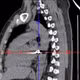

Hình ảnh những còn giòi sống ngọ nguậy trong tai bệnh nhân/Ảnh BV

Qua thăm khám, bác sĩ phát hiện trong ống tai phải bà T. có 5 con giòi sống chen chúc bên xác một con côn trùng, nằm sát màng nhĩ. Ngay sau đó, các y bác sĩ đã tiến hành lấy toàn bộ 5 con giòi cùng xác côn trùng ra ngoài thành công.